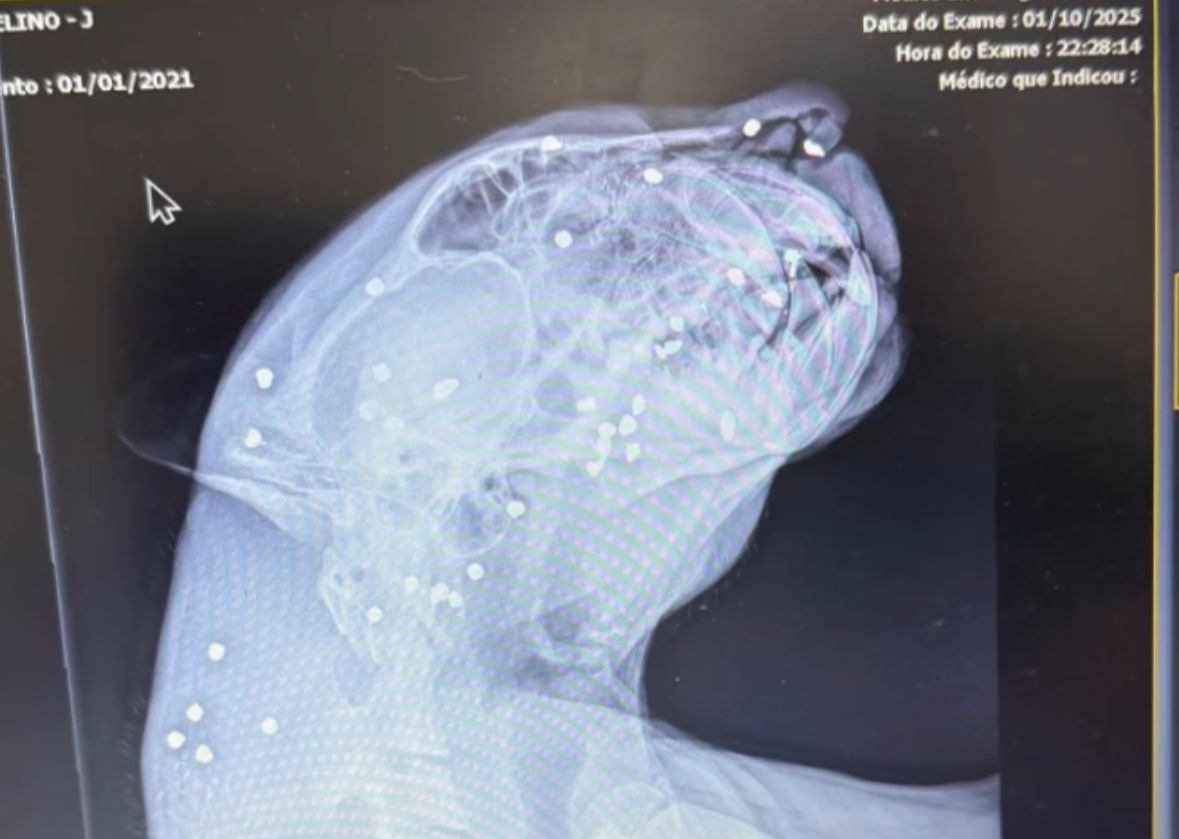

Nas redes sociais, a deputada Joana Darc disse que animal foi atingido com, pelo menos 30 projéteis espalhados pelo corpo, além de dentes quebrados, muito sangue, ferimentos e estava muito debilitado. Ela contou, ainda, que o animal é um macho, que teria passado 8 horas nadando no meio do rio.